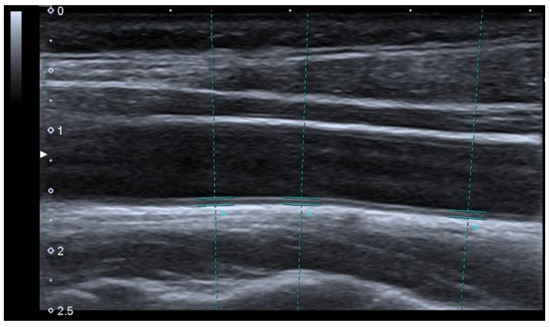

2.3.5. Carotid-Intima Media Tickness

| CIMT (mm) | 0.64 ± 0.17 | 0.47 ± 0.11 | <0.01 * |